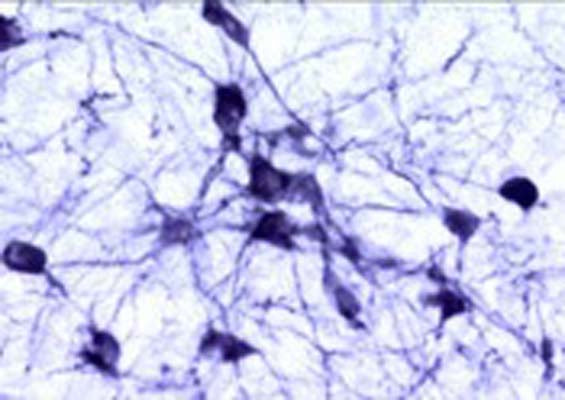

This antiserum stains catecholaminergic neurons, including dendritic processes and fine nerve terminals. We recommend mouse or rat brain containing catecholaminergic neurons as a positive control for this antibody, for example brain stem or striatum.

IHC on brain shows a pattern of staining specific for TH containing neurons. This antibody is known to react with rat, mouse and guinea pig. Cross reactivity with other species has not yet been tested.